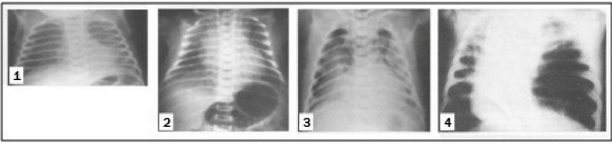

A figura 2 mostra quatro imagens radiológicas. Observe-as com atenção e em seguida assinale a alternativa correta:

Figura 2: Imagens radiológicas do tórax

Fonte: Adaptação de TARANTINO, A. B. Doenças pulmonares. Rio de Janeiro: Guanabara Koogan, 2002. p.261, 262, 264.